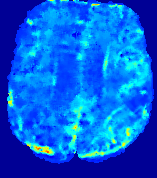

LesionRefer to captionRefer to captionRefer to captionRefer to captionRefer to captionRefer to caption𝐕rgbsubscript𝐕𝑟𝑔𝑏{\bf{V}}_{rgb}Refer to captionRefer to captionRefer to captionRefer to captionRefer to captionRefer to caption𝐕2subscriptnorm𝐕2{\|\bf{V}}\|_{2}Refer to captionRefer to captionRefer to captionRefer to captionRefer to captionRefer to captionRefer to caption3.53.53.52.82.82.82.12.12.11.41.41.40.70.70.70.00.00.0(mm/s)𝑚𝑚𝑠(mm/s)D𝐷DRefer to captionRefer to captionRefer to captionRefer to captionRefer to captionRefer to captionRefer to caption0.0200.0200.0200.0160.0160.0160.0120.0120.0120.0080.0080.0080.0040.0040.0040.0000.0000.000(mm2/s)𝑚superscript𝑚2𝑠(mm^{2}/s)Slice #1Slice #2Slice #3Slice #4Slice #5Slice #6

Figure 3: PIANO feature maps for one stroke patient, where the lesion is located in the left hemisphere. Top row: segmented stroke lesion region (white) on different slices, obtained from ISLES 2017. The corresponding slices for the PIANO feature maps are shown in the following rows.

For a better insight into an estimated velocity field 𝐕𝐕{\bf{V}} and diffusion field 𝐃𝐃{\bf{D}}, we compute the following maps: (1) 𝐕rgbsubscript𝐕𝑟𝑔𝑏{\bf{V}}_{rgb}: Color-coded orientation map of 𝐕=(Vx,Vy,Vz)T𝐕superscriptsuperscript𝑉𝑥superscript𝑉𝑦superscript𝑉𝑧𝑇{\bf{V}}=(V^{x},V^{y},V^{z})^{T}, obtained by normalizing 𝐕𝐕{\bf{V}} to unit length and mapping its 3 components to red, green, blue respectively; (2) 𝐕2subscriptnorm𝐕2\|{\bf{V}}\|_{2}: 222 norm of 𝐕𝐕{\bf{V}}; (3) D𝐷D: scalar field in Eq. 5.

Fig. 3 and Fig. 4 show the PIANO feature maps estimated from two ISLES 2017 patients: all are highly consistent with the lesion in both cases. Details of the blood flow trajectories are revealed in 𝐕rgbsubscript𝐕𝑟𝑔𝑏{\bf{V}}_{rgb} by the ridged patterns and the sharp changes of colors in the unaffected (right) hemisphere, while the flat patterns appearing within the lesion provide little directional information about the velocity and indicate low velocity magnitudes. Velocity magnitudes are more directly visualized via 𝐕2subscriptnorm𝐕2\|{\bf{V}}\|_{2}, from which one can easily locate the lesion where 𝐕2subscriptnorm𝐕2\|{\bf{V}}\|_{2} is low. D𝐷D also indicates lower diffusion values in the lesion, though with less contrast potentially due to the fact that it captures the accumulated effect of CA diffusion at the voxel-level.